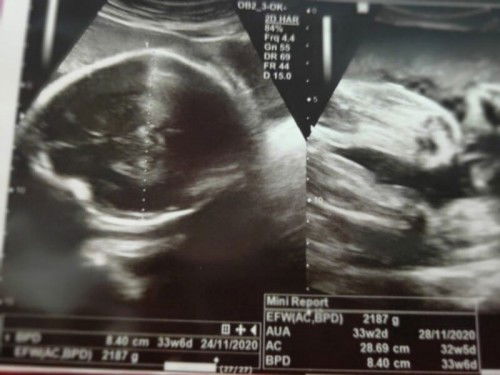

Galau belum ada sinyal dari detun padahal hpl bentar lagi, gemes yg lain udah pada launching, yg ini masih betah didalem, belom ngasih sinyal apa" selain ngilu di miss V. Mohon keikhlasan bunda" TAP. semoga saya bisa lahiran sebelum hpl karena alasan tertentu, secara normal, sehat selamat ibu dan debaynya, lengkap gak ada kekurangan apapun, lancar. amiiin 🙏🏻💕 Dan semoga bunda yg lg nunggu sinyal dr si detun jg disegerakan diberi kelancaran, amiiin 🙏🏻❤️ #firstbaby #121220